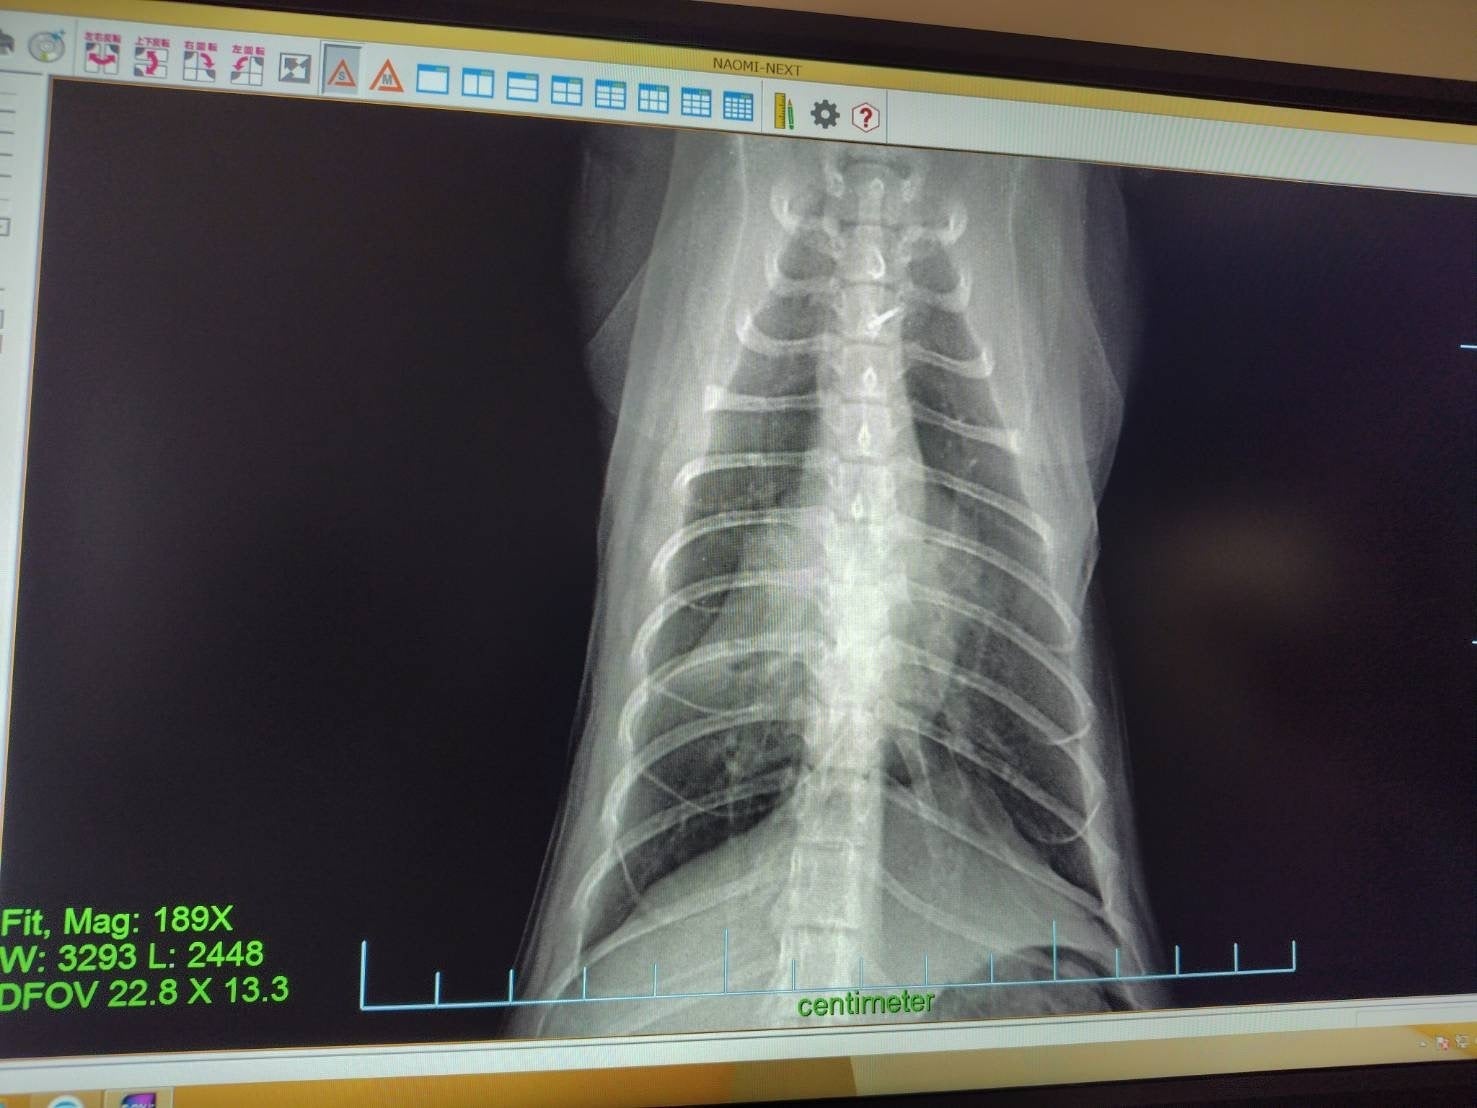

うちに来た時から変な咳をするので病院に連れて行ったところ、以前に風邪を拗らせて肺炎と気管支炎を併発しているとのことです。前にも同じことがありました。美観nekoのタプタプちゃんです。ブリーダーかペットショップで風邪をきちんと治してもらってなくて肺が心臓に癒着してました。風邪をひかないように気を付けておけば喘息も治るのですが、癒着はしたままになります。しっぽくも来た時からメヤニも多いし気にはなってました。これから定期的な治療に入ります。

抗生物質と喘息の治療です。